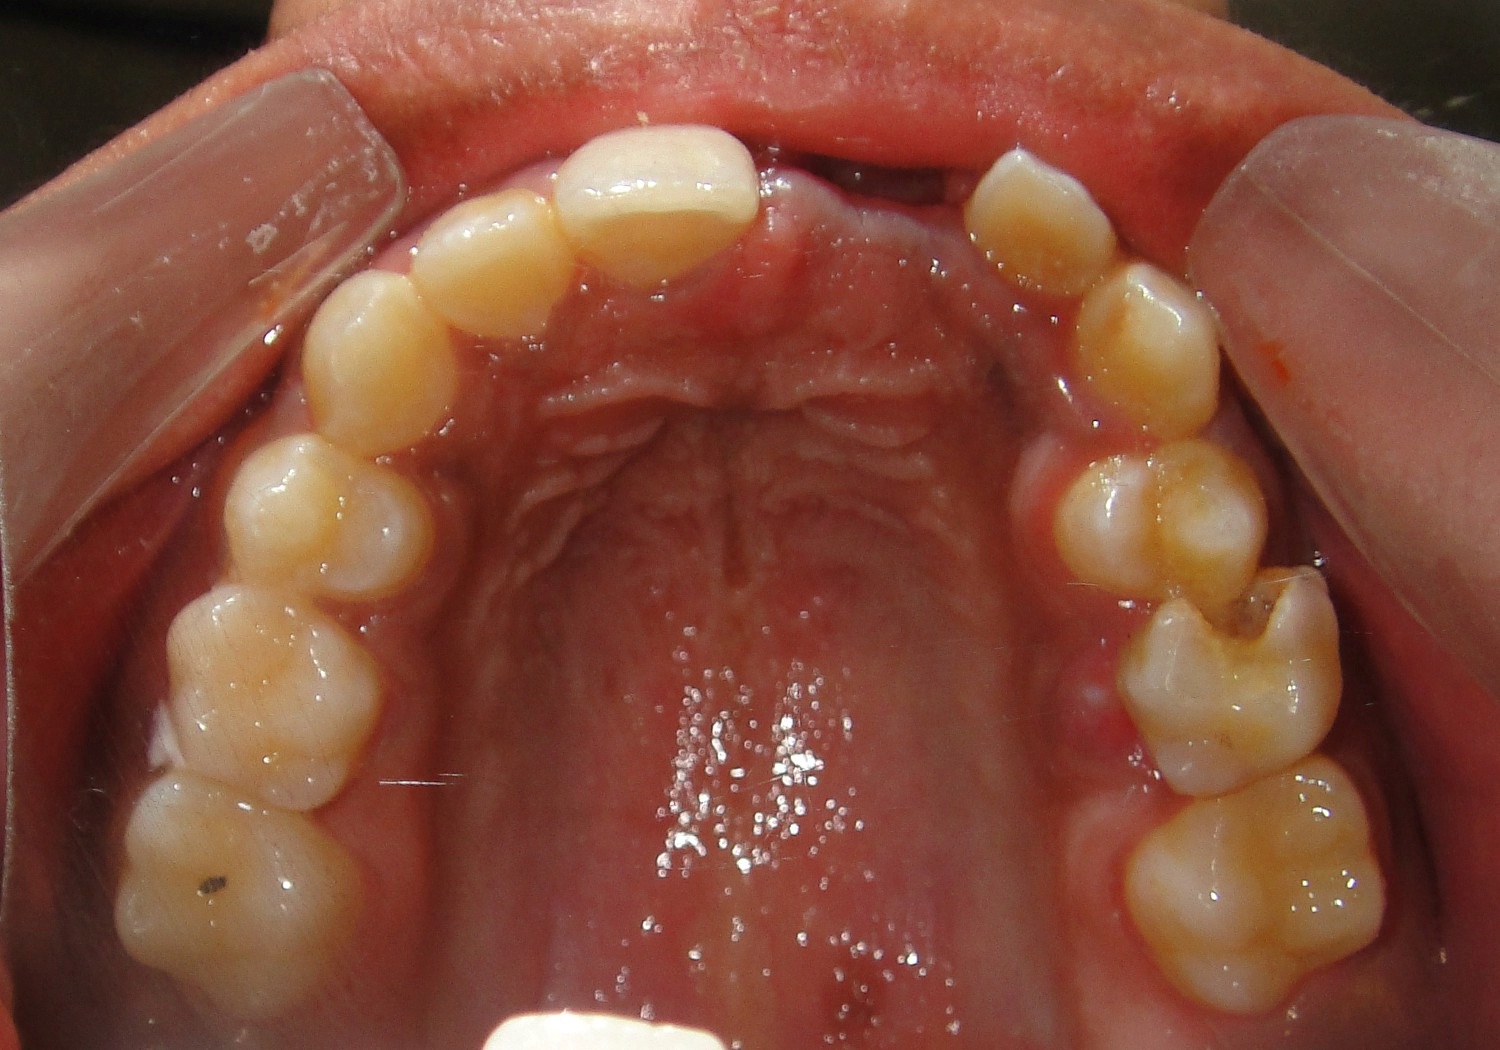

A 12-year-old female patient reported to the Department of Orthodontics of Maulana Azad Institute of Dental Sciences, New Delhi with chief complaint of missing upper front tooth. On clinical examination it was found that maxillary left central incisor (21) was missing [Table/Fig-1]. No significant history of trauma or premature/delayed shedding of primary left central incisor was reported. Panoramic and maxillary occlusal view revealed impacted left central incisor with dilacerated root [Table/Fig-2,3]. Since the contralateral central incisor had erupted fully in the mouth and the root formation of the impacted central incisor was almost complete, it was decided to disimpact the tooth (21). Disimpaction was planned by surgical exposure followed by elastic traction with the help of removable appliance. Since the patient had well aligned upper and lower arches in good occlusion, it was decided to use a modified removable appliance for extrusion of 21. A removable appliance with modified labial bow was fabricated. Labial bow in the anterior region was fabricated with 22 gauge wire and helices were incorporated in the labial bow adjacent to left central incisor region. Retention was provided by the acrylic coverage in the palatal region and by well formed retentive clasps. Surgical exposure of left central incisor was performed by open exposure technique. A bondable button was placed onto the labial surface of exposed left central incisor crown [Table/Fig-4]. Patient was trained to use elastic in triangular fashion to engage button on 21, and two helices of the labial bow, which resulted in an extrusive force of 20 grams for disimpaction of 21[Table/Fig-5] [1]. Patient was advised to change the elastic daily and was reviewed every three weeks. At the end of six months, complete disimpaction of 21 was achieved with the tooth in its optimal alignment into the upper dental arch and in good relation with lower teeth [Table/Fig-6,7]. Post disimpaction panoramic view reveals tooth 21 in the optimal position with respect to maxillary occlusal plane [Table/Fig-8].

Pretreatment intraoral maxillary occlusal photograph showing missing maxillary left central incisor.